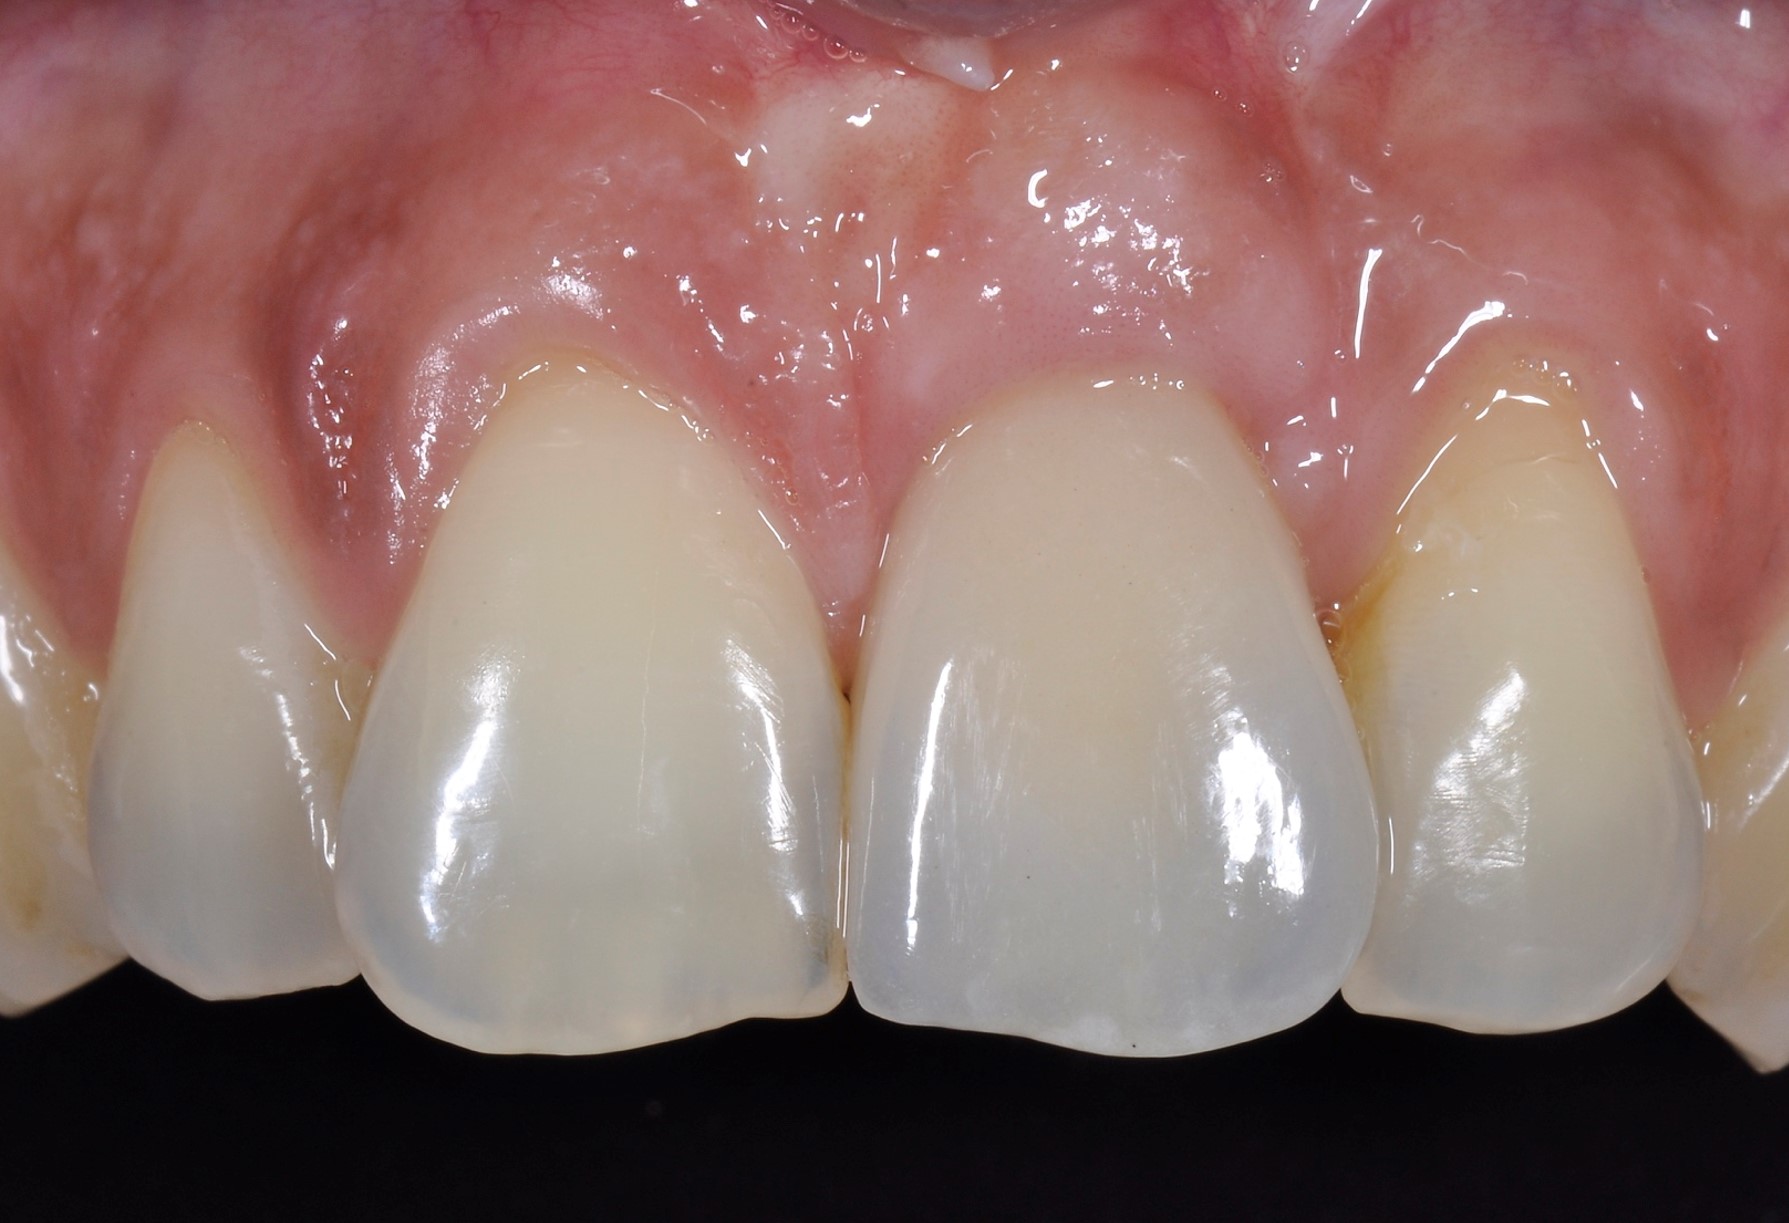

recession on tooth 11